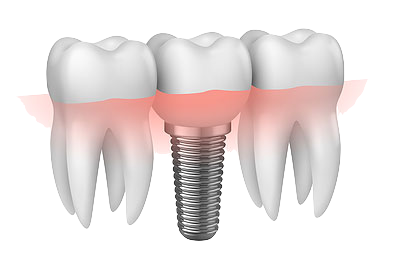

Implantes dentários são suportes que substituem raízes dentárias. É uma estrutura metállica, normalmente feita de titânio, posicionada cirurgicamente no osso que fica logo abaixo da gengiva. A partir disso, o dentista pode posicionar os dentes substitutos sobre ele, permitindo uma melhor estética e função.

O implante está indicado em casos de ausência de dentes, conhecido como agenesia dentária, ou quando houver perda do dente por motivos diversos. Por serem integrados ao osso, os implantes dentários oferecem estabilidade e permitem o encaixe perfeito de próteses sobre ele. Isso evita movimentação e promove conforto ao paciente.

O planejamento de um tratamento completo com implantes normalmente envolvem duas etapas diferentes. Primeiro, uma etapa cirúrgica para a instalação do implante, e a seguir, uma etapa protética, na qual será confeccionada a prótese.

Na primeira etapa, os implantes serão instalados por meio de uma cirurgia. Em seguida, é necessário esperar em torno de 4 a 6 meses para que haja a osteointegração desse implante ao osso. Na segunda etapa, a parte protética começa. Nessa fase, será feito o planejamento de toda a parte da prótese sobre implante, para devolver ao paciente principalmente estética e função.